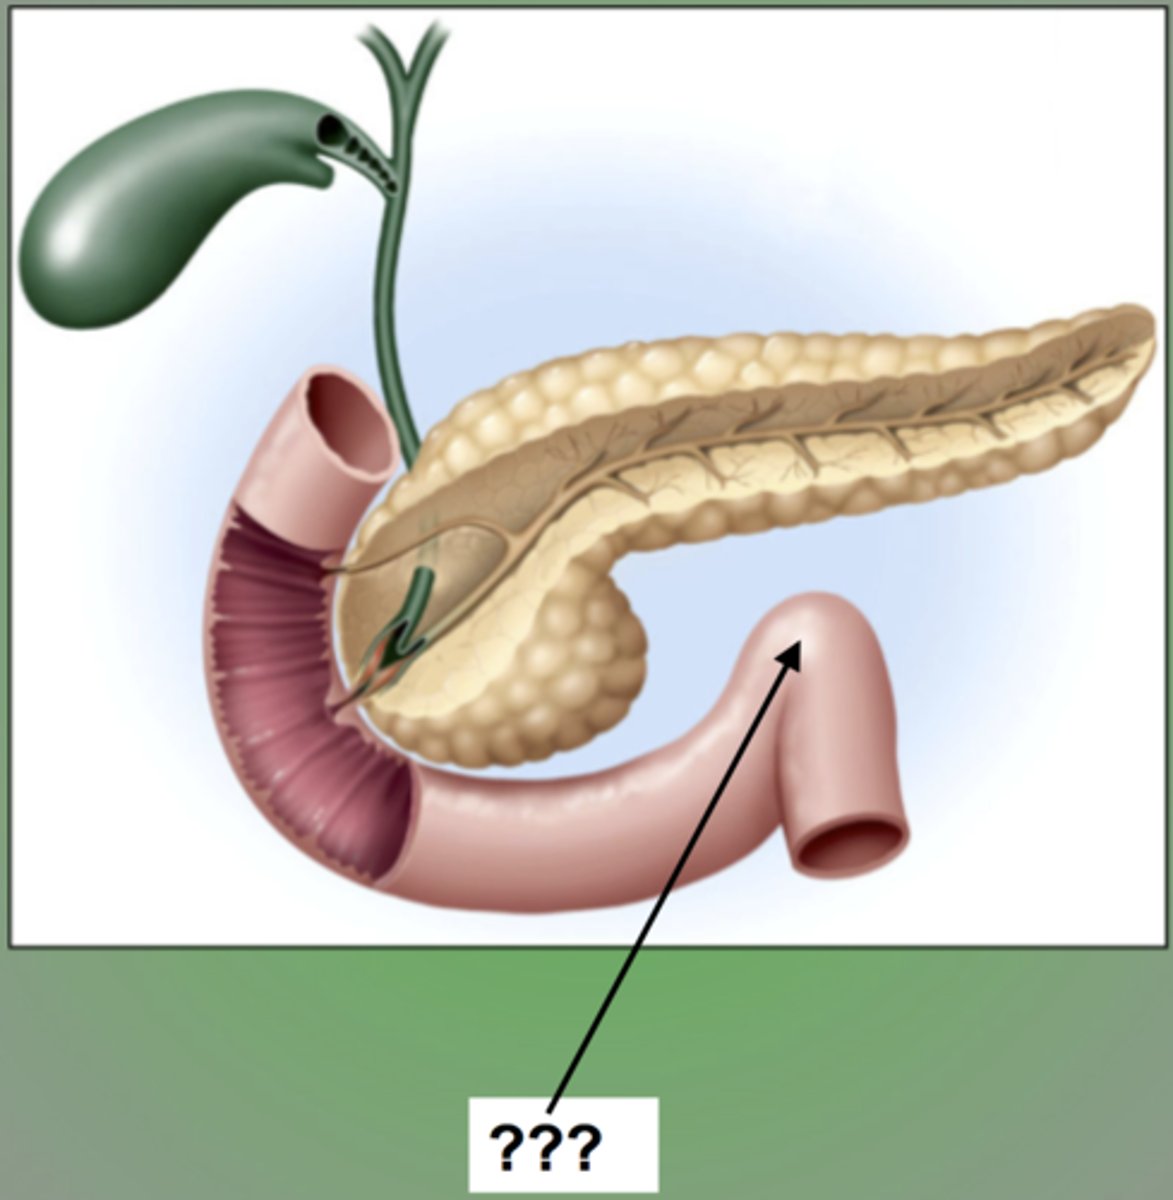

duodenum

major duodenal papilla

opening of ampulla into duodenum

head (of pancreas)

body (of pancreas)

tail (of pancreas)

main pancreatic duct

accessory pancreatic duct

hepatopancreatic ampulla

pancreatic + bile duct

gallbladder